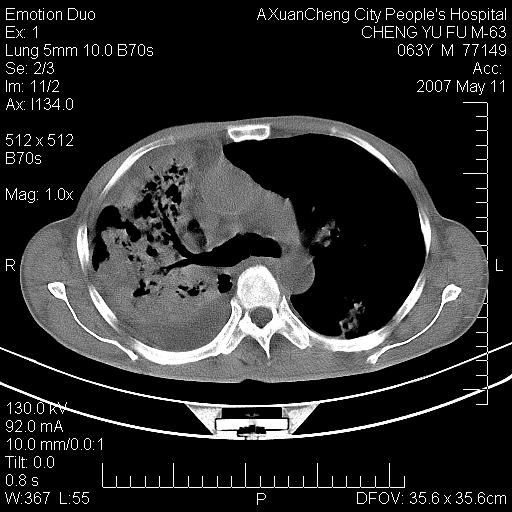

以下是引用小初学者在2007-5-11 19:32:00的发言:[br]1、首先考虑干酪性肺炎支气管播散[br]2、支气管肺泡癌待排

以下是引用zhangzhongshou在2007-5-11 19:30:00的发言:[br]细支气管肺泡癌可能性大。